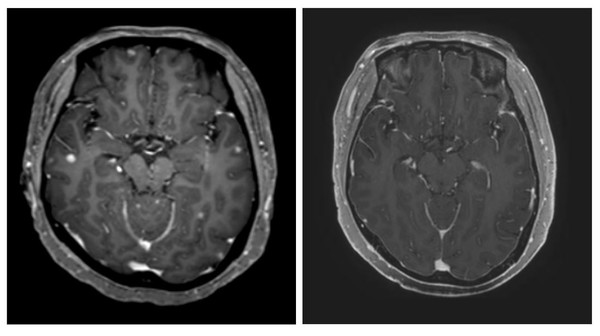

65명에서 추적조사가 힘든 11명을 제외한 54명 중 뇌병변이 1cm 이상으로 CT나 MRI 등 영상촬영을 통해 측정이 가능한 환자는 16명, 뇌병변이 1cm 이하이거나 연수막 전이 등으로 측정이 힘든 환자가 38명이다.

추적조사 결과 타그리소를 복용한 뇌전이 환자 54명에서 암이 줄어든 수치를 나타내는 두개내 반응률은 38.9%, 암이 줄어들거나 크기가 유지되는 두개내 질병조절률은 96.3%였다.

뇌병변 측정이 가능한 16명에서는 두개내 반응률은 62.5%, 두개내 질병조절률은 93.8%로 확인됐다.